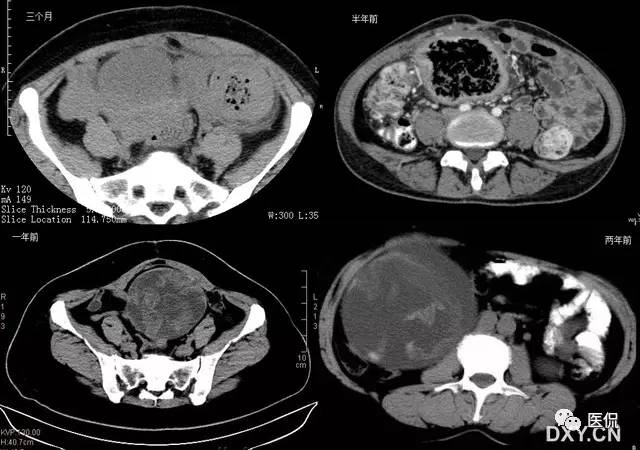

26 蜂窝征

腹腔内残留纱布在人体内引起渗出或液化坏死并纤维包裹形成异物性脓肿(纱布瘤)。纱布瘤的影像特点是:圆形或卵圆形肿块,较大,有完整包膜,薄壁,较少的情况下为后壁,边界较完整,增强后薄膜可以持续强化。不同时期的纱布瘤可以不同的表现:早期(如10各月或半年前)的多表现为蜂窝状;2~5年内一般表现为囊性飘带状;10~20年之后则为实性软组织密度,包膜钙化呈钙化性网状结构。手术过程中残留在人体内的医用纱布所形成的肿瘤样病变。

以下是不同时期纱布瘤的表现: